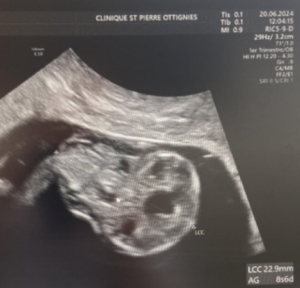

A 33-year-old patient, gravida 1 para 0, presented for a routine examination and dating ultrasound on 06/20/2024. The estimated gestational age was 8 weeks + 6 days. She had no relevant medical history. Her family history was notable for a cousin with trisomy 21. The diagnostic assessment was performed using transabdominal and transvaginal ultrasonography, complemented by three-dimensional (3D) ultrasound. The initial evaluation occurred during a routine first-trimester scan for pregnancy dating at 8+6 weeks of gestation. Ultrasound examination revealed a 23 mm embryo with an enlarged head (Figure 1A). A single gestational sac with two yolk sacs was identified, consistent with a monochorionic–monoamniotic twin pregnancy (Figure 1B).